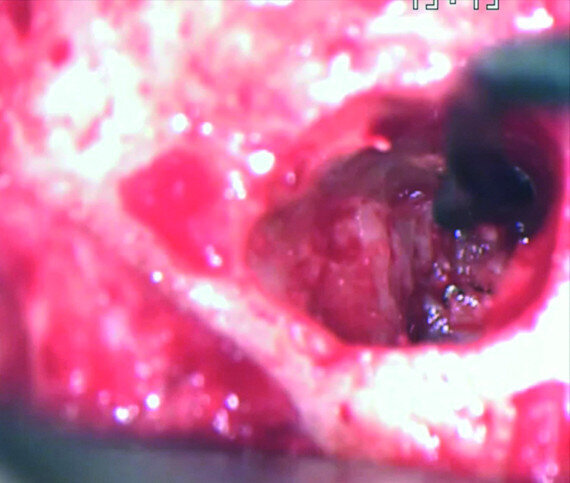

The treatment plan was to try to solve it with a conventional approach and if necessary to perform microsurgery to save the tooth. With the help of H-files, I managed to retrieve the cone from the palatal root, but the files inside the mesial root were impossible to bypass or even to reach with ultrasonic tips. I decided not to overdo it in order to avoid creating an additional problem, like perforating the canal, and decided to seal the canals (Fig. 10). A surgical approach was immediately taken for the mesial canals, cutting 3 mm of the mesial root using the Impact Air handpiece (SybronEndo), and this gave me a direct view of the Schneiderian membrane, where the third file was barely hanging (Figs. 11 & 12). I managed to delicate grab it and to remove it (Fig. 13). Figure 14 shows the postoperative situation, after performing retrograde preparation of the mesial canals.